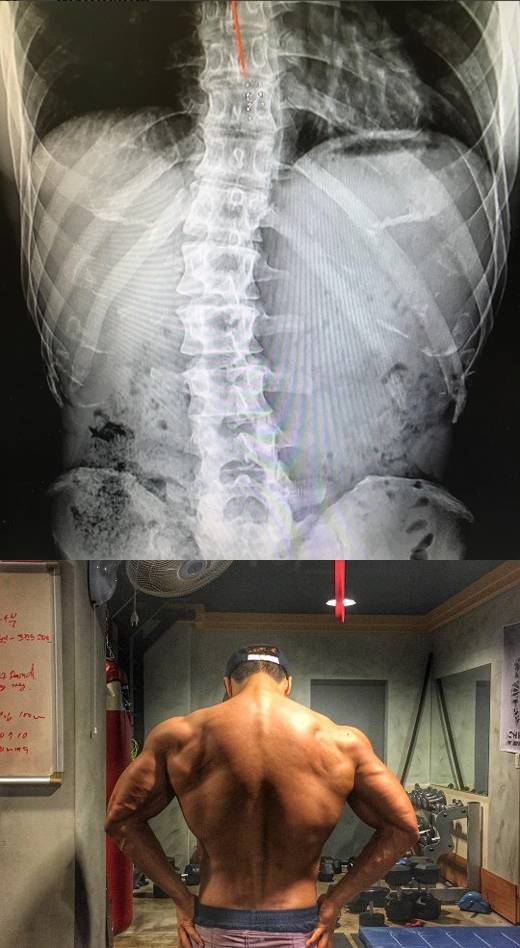

김종국, 근육사진 악플에 엑스레이 공개 "고교 때부터 척추측만증"

김종국은 4일 오후 자신의 인스타그램에 "고등학교 때 처음 허리 통증으로 쓰러졌을 때부터 쭉 가지고 있던 척추측만증. 이런 허리로 어떻게 그런 몸을 만들죠라고 한다. 난 만들었다. 아니 만들고 있다. 이 휘어진 척추, 무언가로는 잡아줘야 하니까"로 시작되는 글을 남겼다.

이와 함께 김종국은 자신의 척추를 촬영한 엑스레이 사진을 덧붙였다.

앞서 3일 김종국은 운동을 마친 뒤 찍은 자신의 등 근육 사진을 공개했다. 대다수의 네티즌은 근육질의 몸매에 감탄하는 모습을 보였지만, 일부 네티즌은 그의 척추측만증 병력을 언급하며 비아냥거리는 반응을 보이기도 했다.